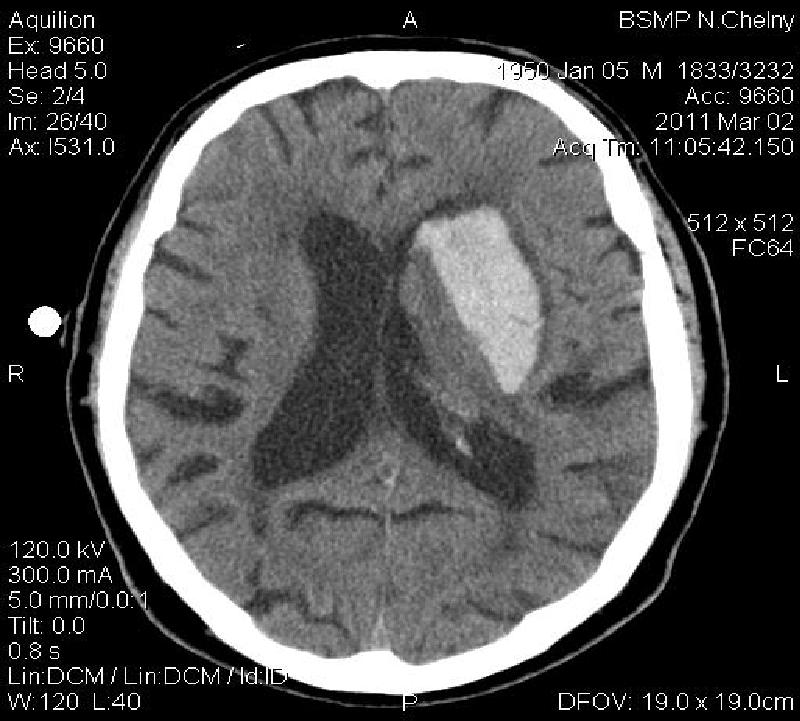

Нейрохирургами проведены две операции по удаление опухолей головного мозга. Навигационная система определила точное месторасположение опухоли и нейрохирург оптимизировал подход к патологическому очагу с минимальными повреждениями. Также проведена одна операция по удалению внутримозговой гематомы с помощью эндоскопического тубуса. При таком кровоизлиянии операционный подход сопровождается разрушением большой зоны мозговой ткани. При использовании навигации операция проводится через 1,5 сантиметровой туннель.